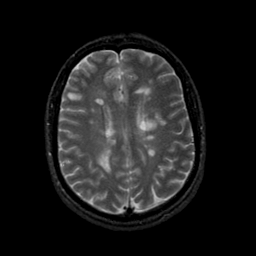

MR Study #9, April 14, 1991 -- Slice #33

[Home][Help][Clinical][Tour 1][Tour 2] Slice 33